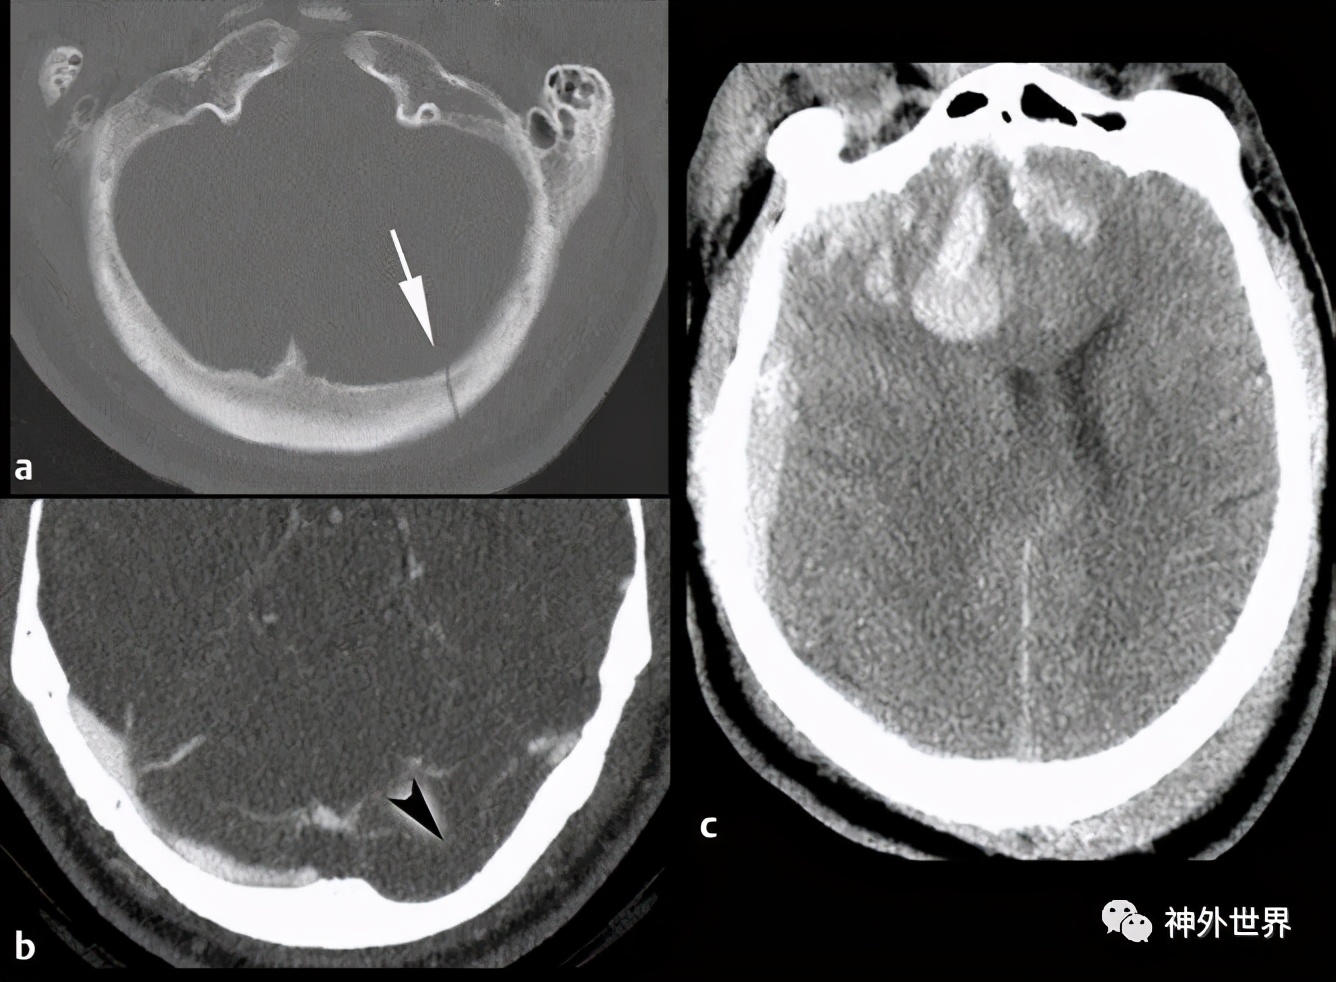

图12:枕骨骨折合并额颞叶对冲伤 。A,CT示左枕骨无移位骨折(箭头);B,CT增强示左侧横窦血栓形成(箭头);C,枕骨骨折对侧额叶挫裂伤并血肿形成和急性右额颞部硬膜下出血